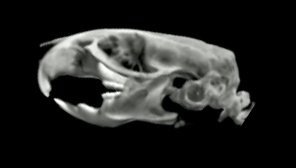

Photo: n/aX-ray Computed Tomography (CT)